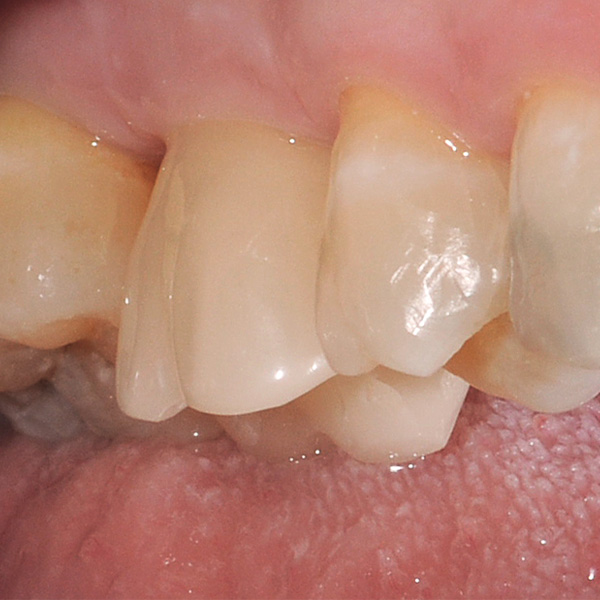

Restauri supportati da impianti sono soggetti a carichi particolarmente elevati. Dopo l‘estrazione e l‘impianto al paziente manca l‘apparato di fibre elastiche del letto dentale naturale. Per questo motivo le forze di masticazione non vengono assorbite, ma trasmesse direttamente sul restauro, l‘impianto, l‘osso e la dentatura antagonista. La ceramica ibrida VITA ENAMIC ha una struttura a reticolo duale in ceramica (86 % in peso) e polimero (14 in peso). Ne risulta un‘elasticità simile alla dentina e la capacità do assorbire le forze di masticazione. Il blocchetto policromo VITA ENAMIC multiColor in geometria EMC-16, grazie alla sua elevata dimensione verticale, consente di realizzare corone-abutment monoblocco, monolitiche anche nel caso di osso atrofizzato. L‘odontoiatra Professor Dr. Alexander Hassel mostra in questo contributo come riabilita una paziente con questa forma di restauro.